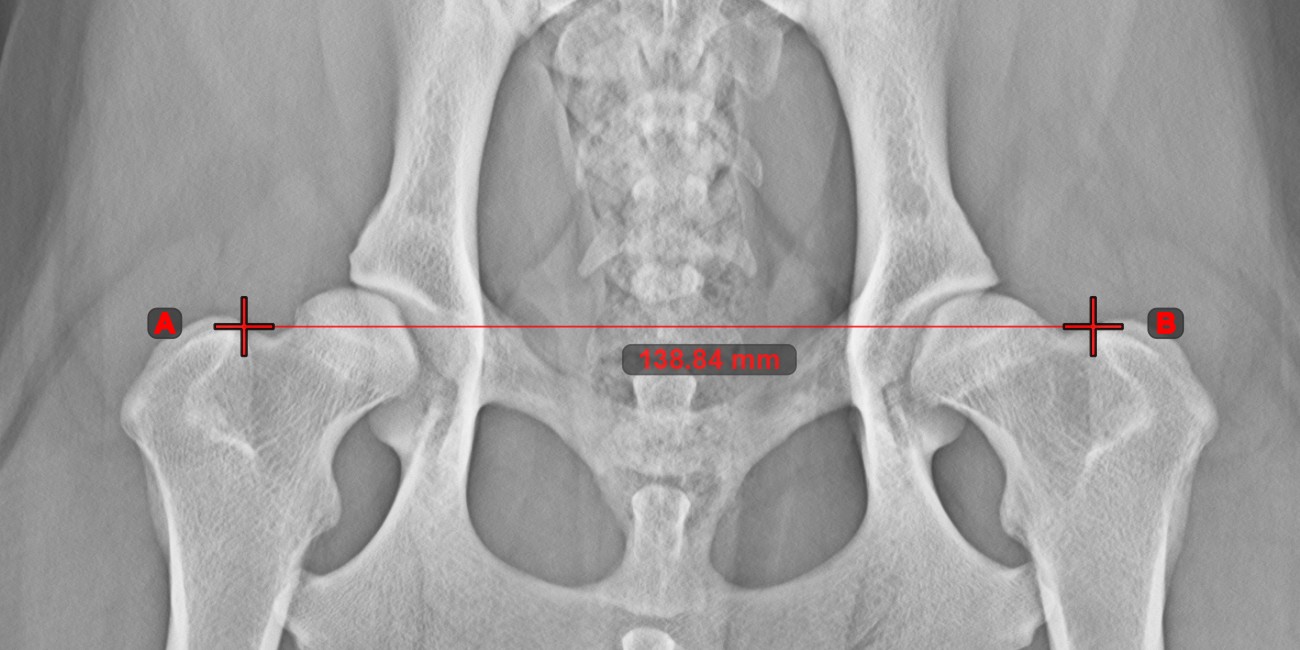

Linienmessung¶

Erstellen Sie eine Linienmessung, um den Abstand zwischen zwei Punkten mit hoher Genauigkeit zu berechnen.

Wählen Sie das Werkzeug Linienmessung

aus und weisen Sie es einer der verfügbaren Maustasten zu. Setzen Sie die Start- und Endpunkte in der Szene oder wählen Sie sie aus bereits vorhandenen Punkten im Bild aus. Der Abstand zwischen den beiden Punkten wird automatisch anhand der Standardkalibrierdaten oder der durch die Längenkalibrierung-Messung neu kalibrierten Daten berechnet.

Ändern Sie den Start- und Endpunkt mit dem Werkzeug Objekt auswählen/verschieben

. Der Abstand zwischen den beiden Punkten wird automatisch neu berechnet.